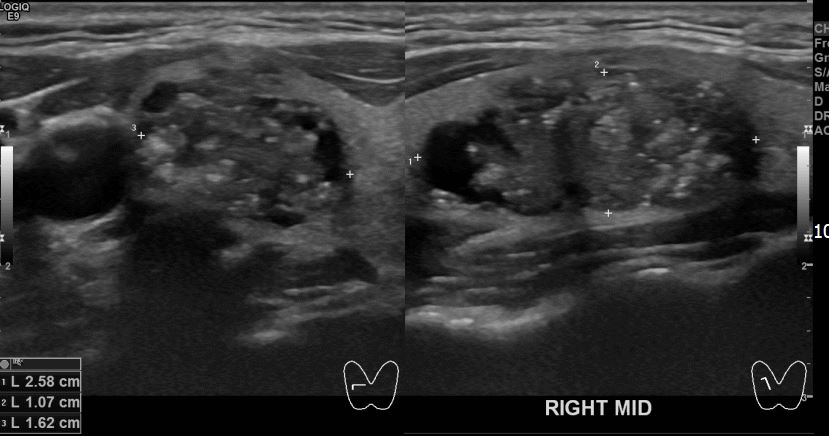

상기환자 외부검진이상으로 내원하신 30대초반 여성분으로 우엽 의심스러운혹 세포검사진행후 갑상선암으로 진단되었습니다